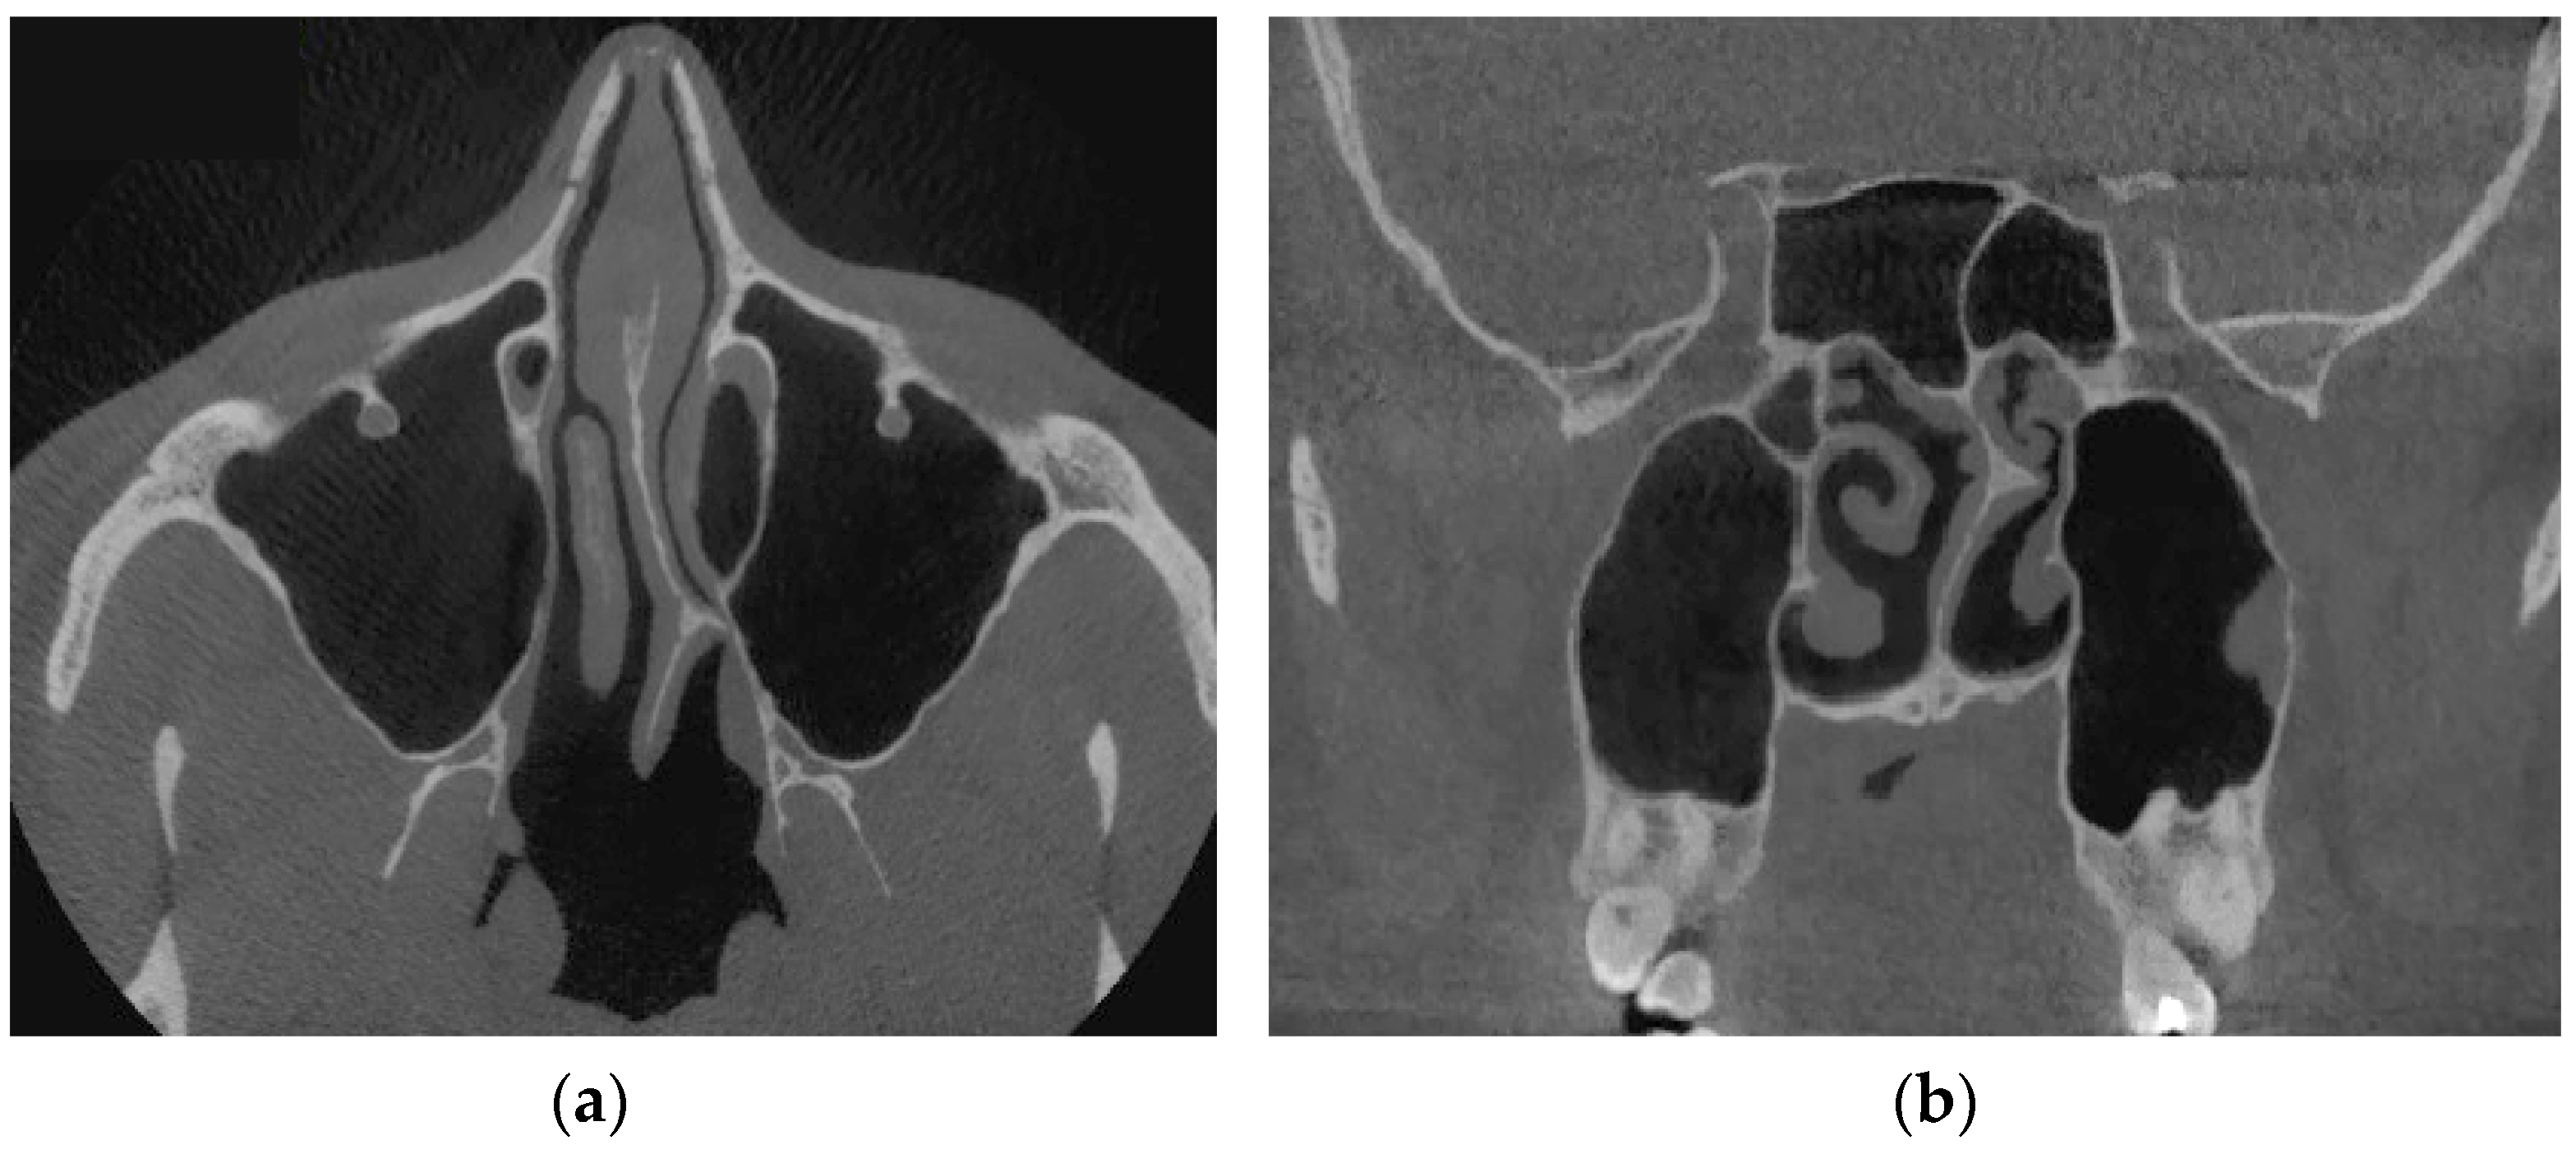

Verification of rhinomanometric data should be performed on the basis of tomographic data of the conditional norm and pathological conditions, which, due to various factors, affect nasal aerodynamics in different ways. Thus, in Figure 12 it is possible to see the characteristic tomographic sections of the nasal cavity at the conditional norm in the axial (Figure 12a) and frontal (Figure 12b) planes.

Figure 13 shows tomographic data of a patient with a curvature of the nasal septum to the left in the middle section, where you can clearly see a large change in configuration in the middle section of the nasal cavity on both axial (Figure 13a) and frontal (Figure 13b) sections.